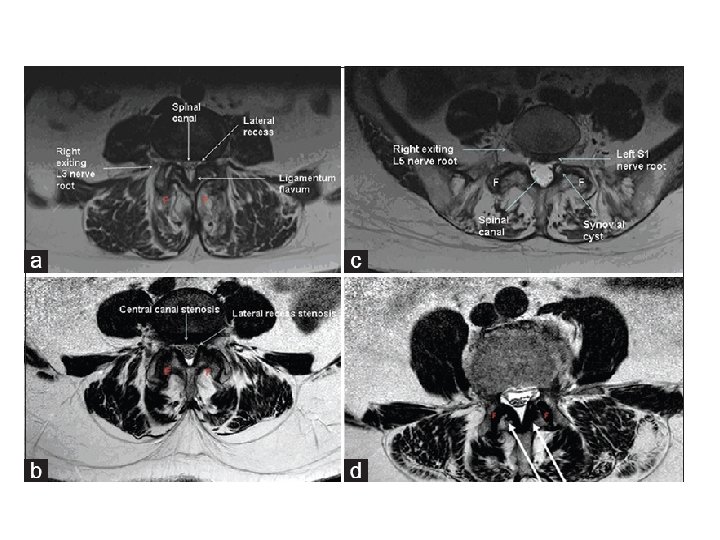

• Pathophysiology : Compression can lead to either foraminal stenosis mainly , lateral recess stenosis or rarely central stenosis. § foraminal stenosis : mainly : – Adult isthmic spondylolisthesis at L 5/S 1 often leads to radicular symptoms caused by compression of the exiting L 5 nerve root in the L 5 -S 1 foramen. compression can be caused by : • hypertrophic fibrous repair tissue of the pars defect • uncinate spur formation of the posterior L 5 body • bulging of the L 5/S 1 disc § lateral recess stenosis • caused by facet arthrosis mainly or hypertrophic ligamentum flavum. § central stenosis • rare due to fact that these slips are usually only Grade I or II

- neurologic symptoms caused mainly by central and lateral recess stenosis and to a less degree foraminal stenosis. § Central and lateral recess stenosis : • degenerative slip at L 4/5 will affect the descending L 5 nerve root in the lateral recess. - caused by slippage, hypertrophy of ligamentum flavum, and encroachment into the spinal canal of osteophytes from facet arthrosis.